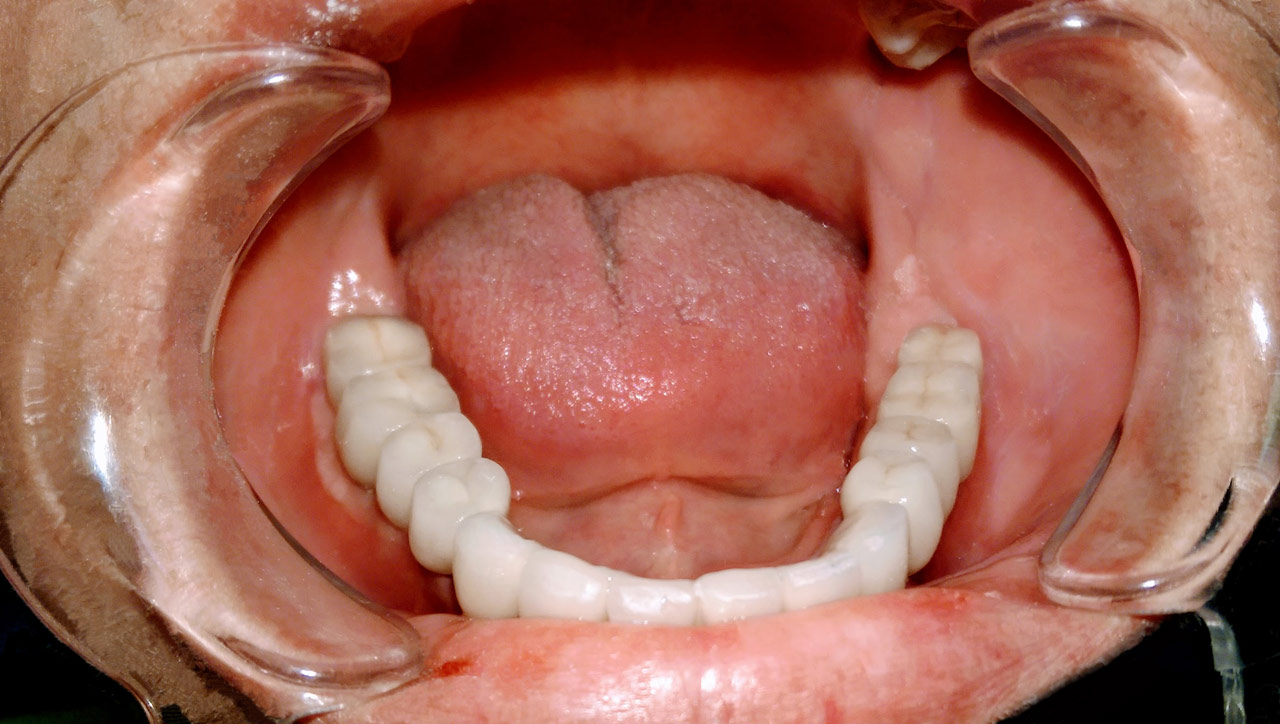

Teljes fogatlanság helyreállítása 2 nap alatt

Teljes fogatlanság helyreállítása 2 nap alatt azonnal terhelhető svájci IHDE implantátumokkal és PMMA műanyag hidakkal. Intraorális szkennerrel vettünk lenyomatot az implantáció után, és erre a digitális mintára készítette el a fogtechnika a hidak digitális tervezését, majd faragta ki műanyagból. Ezt a gyors munkát az azonnal terhelhető implantátumok és a digitális lenyomat, tervezés segítségével tudtuk megcsinálni mindössze 2 nap alatt. Dr. Kelemen Péter és a Symbion Fogtechnika munkája.